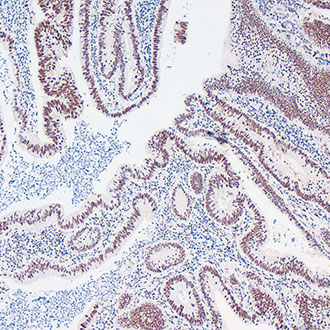

CDX-2

CDX-2 -